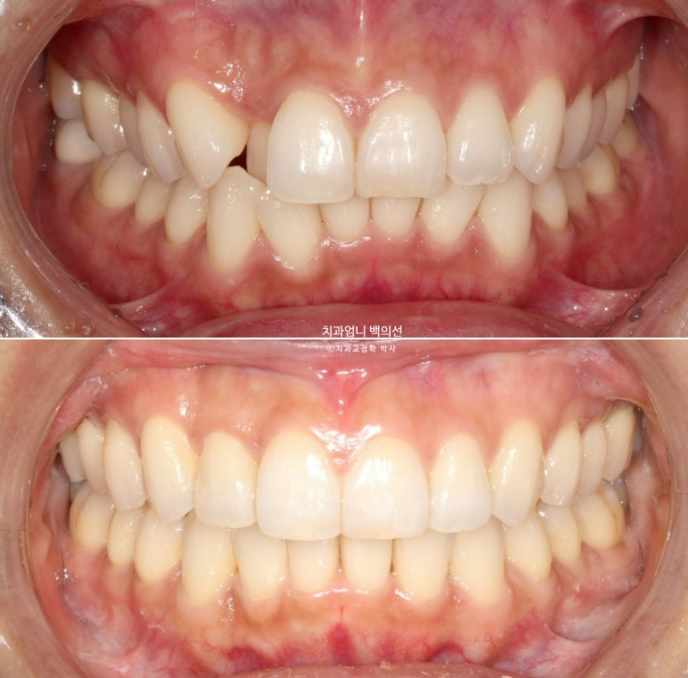

위 아래 앞니 중심선 불일치가 보입니다.

엑스레이를 찍어보면 뼈의 비대칭은 없으나 덧니때문에 위 앞니 중심선이 한쪽으로 쏠려서 비대칭감을 느끼는 상태입니다.

입천장으로 들어가있는 측절치는 아랫니와 반대로 물리는 반대교합 입니다.

멀리서 오시기에 내원간격 때문에 인비절라인 치료를 선택하셨고 23년 10월부터 24년 8월까지 첫세트 44개 장치를 모두 낀 후 모습입니다

중심선은 잘 맞으나 입천장에 위치했던 축절치가 아직 완벽하게 제자리를 찾지 못했습니다.

위 아래 앞니 중심선은 정확히 매치가 됩니다.

덧니는 잘 배열되었습니다.